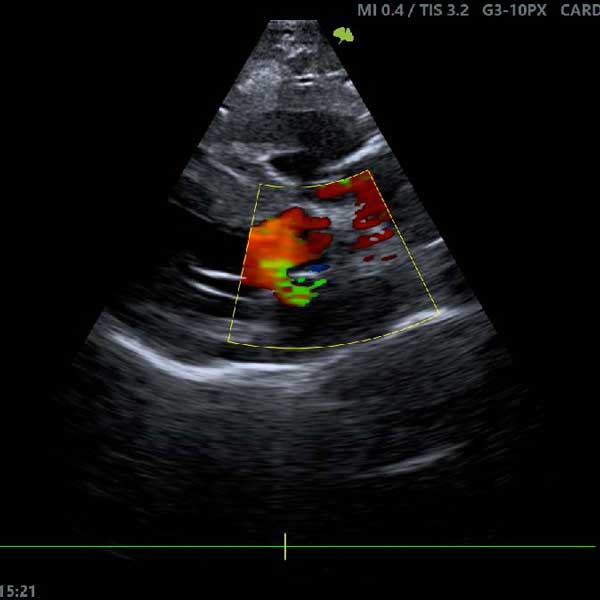

2. Échographie cardiaque (échocardiographie)

Pour les animaux présentant des symptômes tels que de la toux, une fatigue inhabituelle ou des difficultés respiratoires, l’échographie cardiaque est un examen clé. Elle permet de visualiser les structures du cœur et d'évaluer son fonctionnement.

Exemples de pathologies détectées :

• Insuffisance cardiaque.

• Malformations congénitales.

• Maladie valvulaire dégénérative.